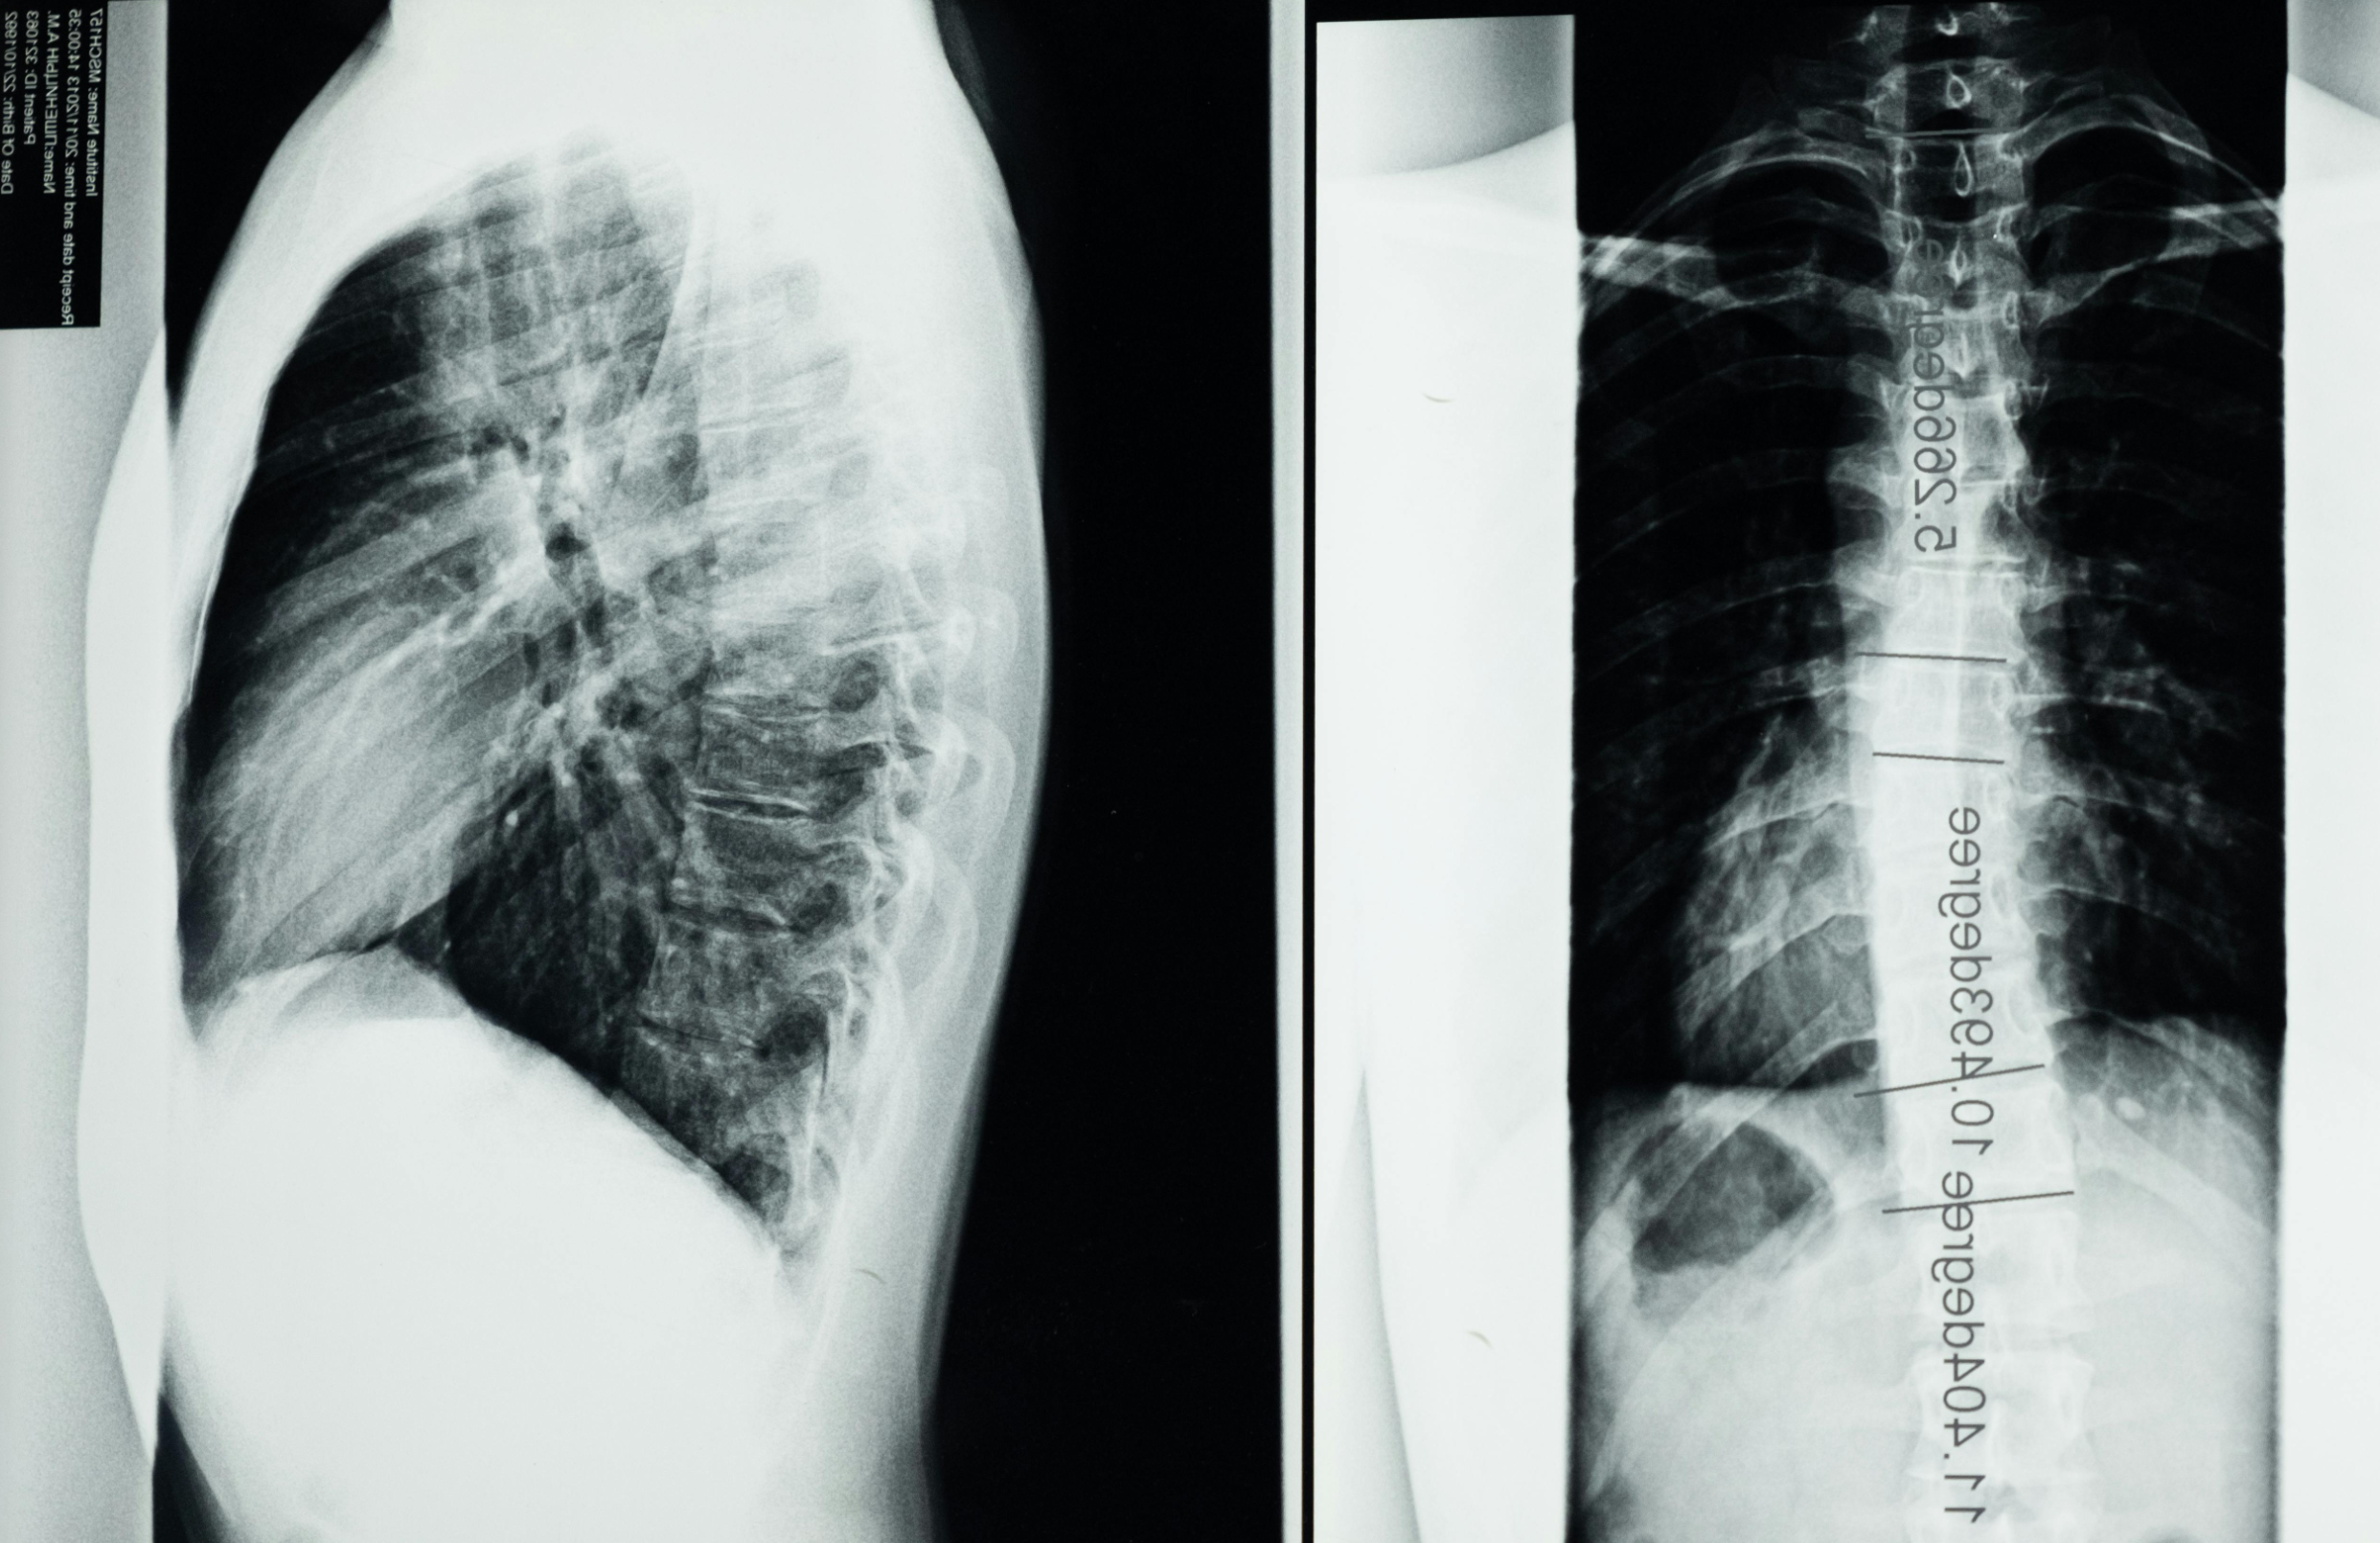

허리 앞굽음 자세 : 앞굽음 자세는 허리엉치각의 증가로 허리뼈 앞굽음 증가, 골반의 엉덩관절 굽힘 이 나 골반의 앞쪽 경사 증가로 허리뼈 앞굽음은 증가한다. 이에 따라 머리가 앞으로 나오고 등뼈 뒤 굽음이 증가한 것을 자주 볼 수 있는데 이것을 앞 굽은 자세라고 부른다. 엉덩관절 굽힘근 과 허리뼈 퍼온 글의 가동성 감소, 신장하고 약화한 복 부근으로 인한 근 수행력의 손상, 앞세로인대의 스트레스, 척추사이원반의 뒤 공간이나 척추사이구멍이 좁아져 신경 몸통이나 신경과 연관된 혈관과 경질막의 압박으로 나타나기도 하고 척추나 척추사이원반의 퇴행성 변화의 주원인이 된다. 척추 관절의 압박. 관절면을 통해 체중 지지가 증가하면 관절 염증과 윤활액의 염증을 만들어 내는 원인이 되고, 이것이 수정되지 않는다면 결국 퇴행성 변화가 가속화될 수 있다.